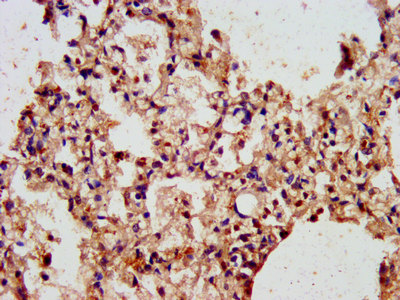

IHC image of CSB-PA002070LA01HU diluted at 1:300 and staining in paraffin-embedded human lung tissue performed on a Leica BondTM system. After dewaxing and hydration, antigen retrieval was mediated by high pressure in a citrate buffer (pH 6.0). Section was blocked with 10% normal goat serum 30min at RT. Then primary antibody (1% BSA) was incubated at 4°C overnight. The primary is detected by a biotinylated secondary antibody and visualized using an HRP conjugated SP system.